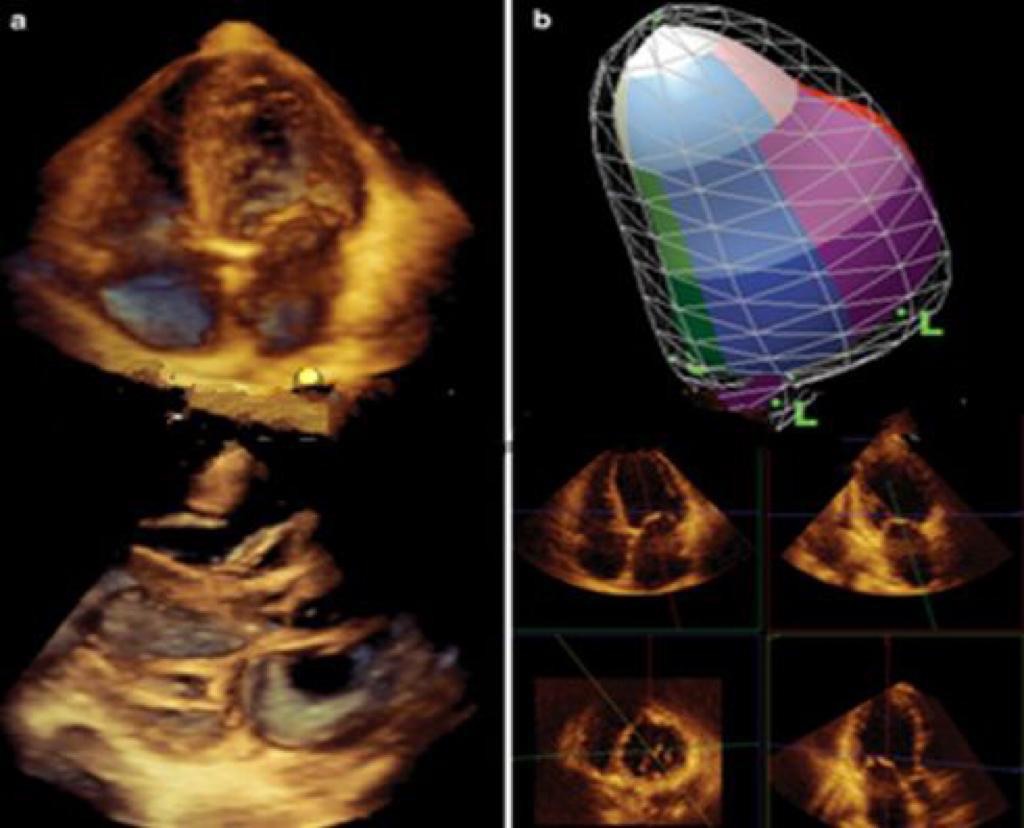

Трехмерная эхокардиография – это диагностический метод, который позволяет детально рассмотреть структуру сердца при операциях на клапанах сердца.

Раньше для исследований применялся метод двухмерной эхокардиографии, но он имел существенный недостаток: врачи видели все в одной плоскости. Когда специалисты перемещали датчик, то они начинали видеть картинку с другого угла, но предыдущее изображение терялось. При выполнении трехмерной эхокардиографии специалисты стали видеть работу структур сердца единым комплексом. То есть когда на экран выводятся клапаны сердца, можно увидеть все его части под разными углами и как они совместно работают. Работу сердца видно в формате 3D в режиме реального времени.

Освоение нового метода стало возможно благодаря закупке новых ультразвуковых аппаратов экспертного класса. Трехмерная эхокардиография выполняется непосредственно во время операции. К аппарату УЗИ подключается чрезпищеводный датчик. Выполняется 3D, после чего врачи решают, какая операция будет проведена на клапанах сердца, проводят вмешательство, после этого процедуру повторяют и проверяют, как выполнена реконструкция.